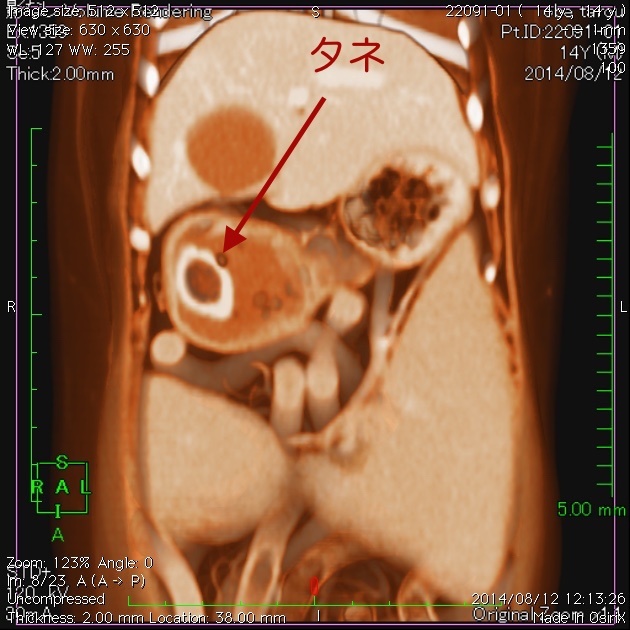

CT検査では膵臓にしこりは見つからなかったので、とりあえずは一安心だったんですが・・・。CT検査で胃の中に大きな種があることが分かりました。

上の画像はCTの断層の画像ですが、下の画像は3D校正したCT画像です。見事に種が写ってますね。一番下は内視鏡で摘出しているタネです。胃内異物はとても多い病気ですが、胃内にある場合は、よほど大きくなければ手術ではなく内視鏡で摘出しています。